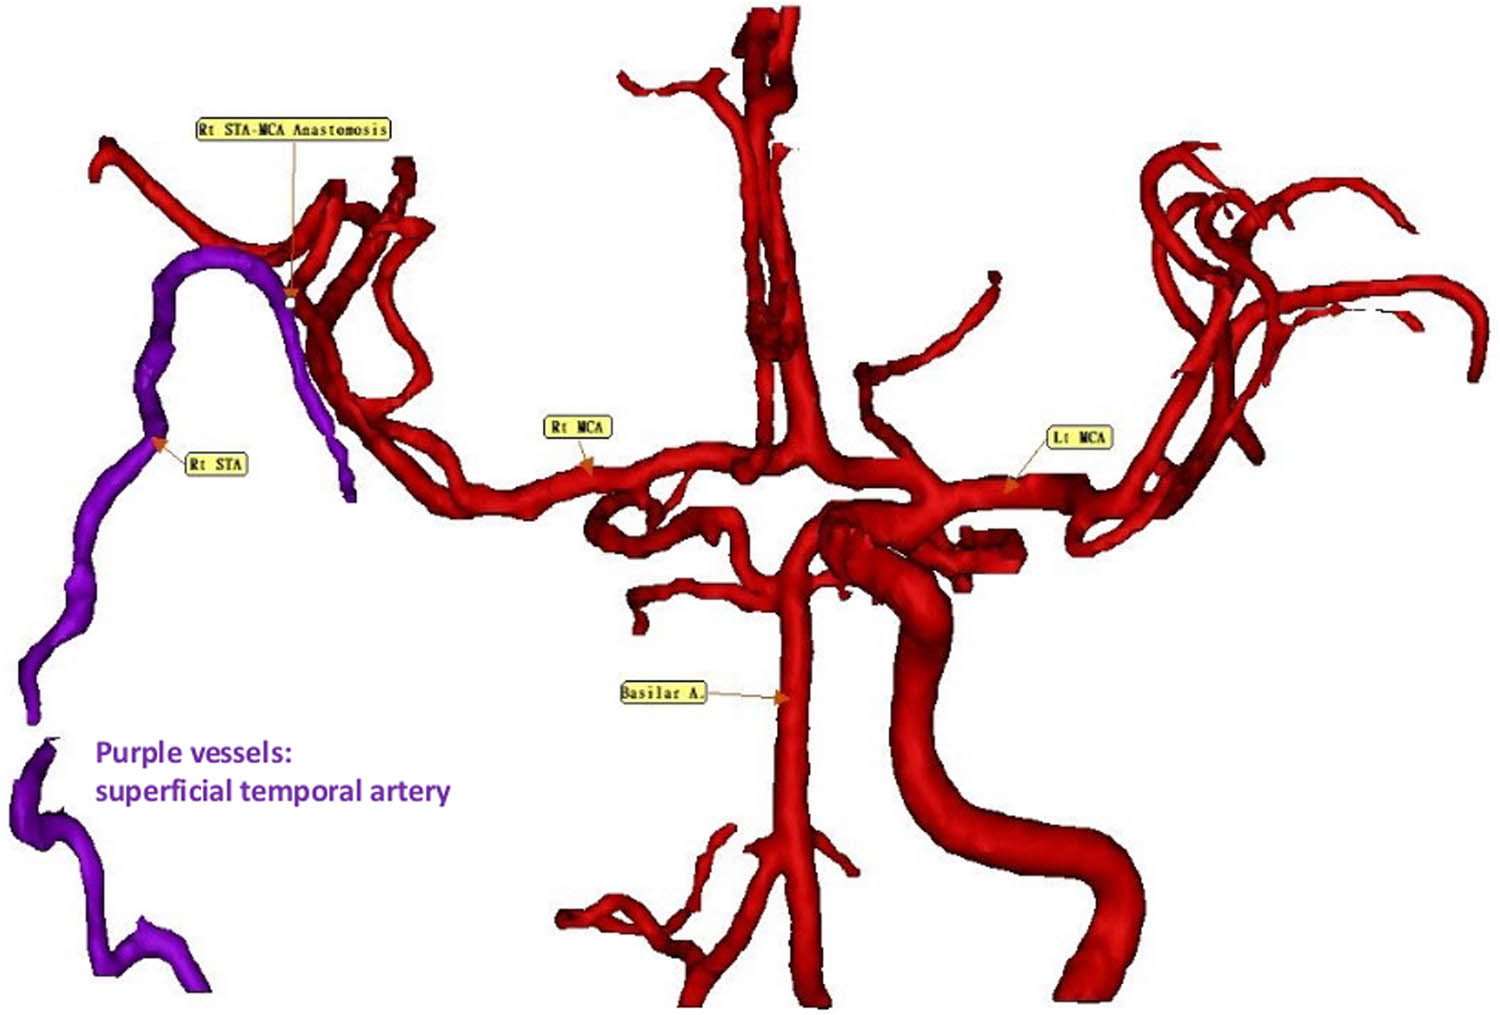

Cerebral vascular imaging before surgery confirmed right ICA occlusion prior to the procedure. On November 13, 2024, postoperative imaging following STA–MCA bypass demonstrated enhanced cerebral perfusion, with no evidence of new ischemic lesions, indicating the absence of perioperative infarction (Figure 4). On January 13, 2025, adjunctive therapy with hydrogen–rhodiola capsules was administered. On March 13, 2025, after two months of adjuvant therapy with hydrogen-rhodiola capsules, postoperative imaging demonstrated improved cerebral perfusion, correlating with the notable neurological recovery of the patient. Specifically, motor function improved from severe left-sided weakness (Medical Research Council grade 1) to near-complete recovery, with MRC grade 5 in the left upper limb and grade 4 in the left lower limb.

Three-dimensional reconstructions of the cerebral vasculature. Follow-up imaging on January 14, 2025, after STA–MCA bypass surgery, reveals improved cerebral perfusion. No new ischemic lesions are observed, confirming the absence of perioperative infarcts. Purple vessels: STA.